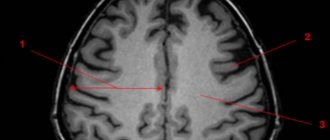

Особенности МР-диагностики очаговых изменений вещества мозга

Как правило, о наличии очаговых изменений в веществе мозга становится известно после того, как пациент прошел МРТ. Для уточнения характера поражения и дифференциальной диагностики исследование может быть проведено с контрастированием.

Множественные очаговые изменения более характерны для инфекций, врожденной патологии, сосудистых расстройств и дисметаболических процессов, рассеянного склероза, тогда как единичные очаговые изменения возникают после перенесенных инсультов, перинатальных поражений, отдельных видов травм, метастазировании опухолей.

Очаговые изменения вещества мозга дистрофического характера на фоне возрастной инволюции представлены МР-признаками:

- Перивентрикулярные (вокруг сосудов) «шапочки» и «полосы» – обнаруживаются снаружи от боковых желудочков, возникают из-за распада миелина и расширения околососудистых пространств, разрастания клеток глии под эпендимой желудочков;

- Атрофические изменения полушарий с расширением борозд и желудочковой системы;

- Единичные очаговые изменения в глубоких отделах белого вещества.

Множественные очаговые изменения дисциркуляторного характера имеют характерное глубокое расположение в белом веществе мозга. Описанные изменения будут более выражены, а симптоматика энцефалопатии прогрессирующей при сопутствующей возрасту гипертонии.